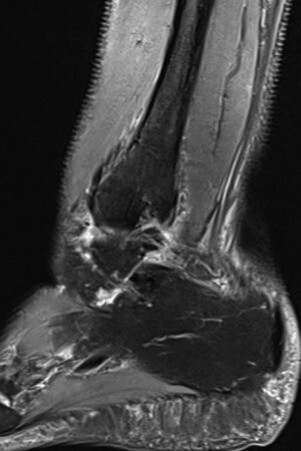

Vor der Behandlung zeigte der AOFAS Score 40 Punkte, nach drei Behandlungen lag der Score bei 70 und nach fünf Behandlungen ermittelten wir einen Wert von 100. Somit war der Wert eines gesunden Sprunggelenkes erreicht. Zur Ermittlung der Schwellung haben wir den Umfang an der Fibulaspitze im Seitenvergleich gemessen, der vor der Behandlung an der frakturierten Fibula um ca. 10% größer war als auf der Gegenseite. Nach den ersten drei Behandlungen waren die Umfänge im gleichen Bereich identisch. Die anfänglich deutlich limitierte Dorsalextension sowie Hebung des Fußaußenrandes des betroffenen Sprunggelenkes war nach der gesamten Therapie wieder seitengleich normwertig. Der anfänglich intensive Klopfschmerz wurde bereits nach der zweiten Behandlung nicht mehr angegeben. Auch das alltägliche Schmerzlevel verringerte sich nach jeder Behandlung deutlich, sodass bereits nach drei Behandlungen mittels ESWT sowohl mit als auch ohne Orthese kaum noch Schmerzen vorhanden waren und bereits eine Schrittzahl von ca 10.000 am Tag möglich war. Radfahren war ab der 3. Behandlungswoche erlaubt und der Patientin beschwerdefrei möglich. Nach drei Behandlungen (ab der 4. Woche) wurde bereits von der Stabilorthese auf den elastischen Anteil reduziert. Im Rahmen der Trainingstherapie wurden ab der 4. Wochen schon kurze Läufe (10- 15 Min.) auf dem Laufband begonnen, die ebenfalls beschwerdefrei toleriert wurden. Am Ende der Behandlung legte die Patientin bereits 15.000 Schritte am Tag zurück. Ein zwischenzeitlich durchgeführtes Kontroll-Röntgenbild zeigte keine sekundäre Dislokation. Die sechs Wochen nach Beginn der Therapie durchgeführte MRT zeigte eine nahezu vollständige Konsolidierung des Knochens (vgl. Abb. 3 und Abb. 4).

Abbildung 4. Sagittales Schnittbild (sag/pd).